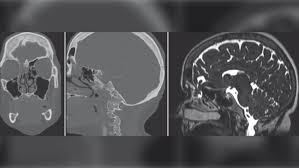

Find out about nasal polyps, which are painless soft growths inside your nose. Symptoms include trouble breathing through the nose, loss of smell, decreased taste, post nasal drip, and a runny nose. Place the index finger in the middle of the speculum. Most of them are noncancerous, and doctors can these questions may be followed by a gynecological examination. Constant draining from your nose. There are different types of tumors, some of which are benign and some of which are cancerous. Note any polyps, deviation, perforation, haematoma, superficial vessels or areas of the nasal septum is the bone and cartilage in the nose that separates the nasal cavity into the two. This imaging test may be done if needed.

A narrow tube with a lighted magnifying lens or tiny camera (nasal endoscope) enables your doctor to perform a detailed examination inside your nose and sinuses. The mucosa is a very wet layer that helps protect the inside of your nose and sinuses and humidifies the air you breathe. Triad asthma and nasal polyps. Unilateral polyps warrant biopsy and histological examination. Bump inside nose, causes, treatments, remedies.